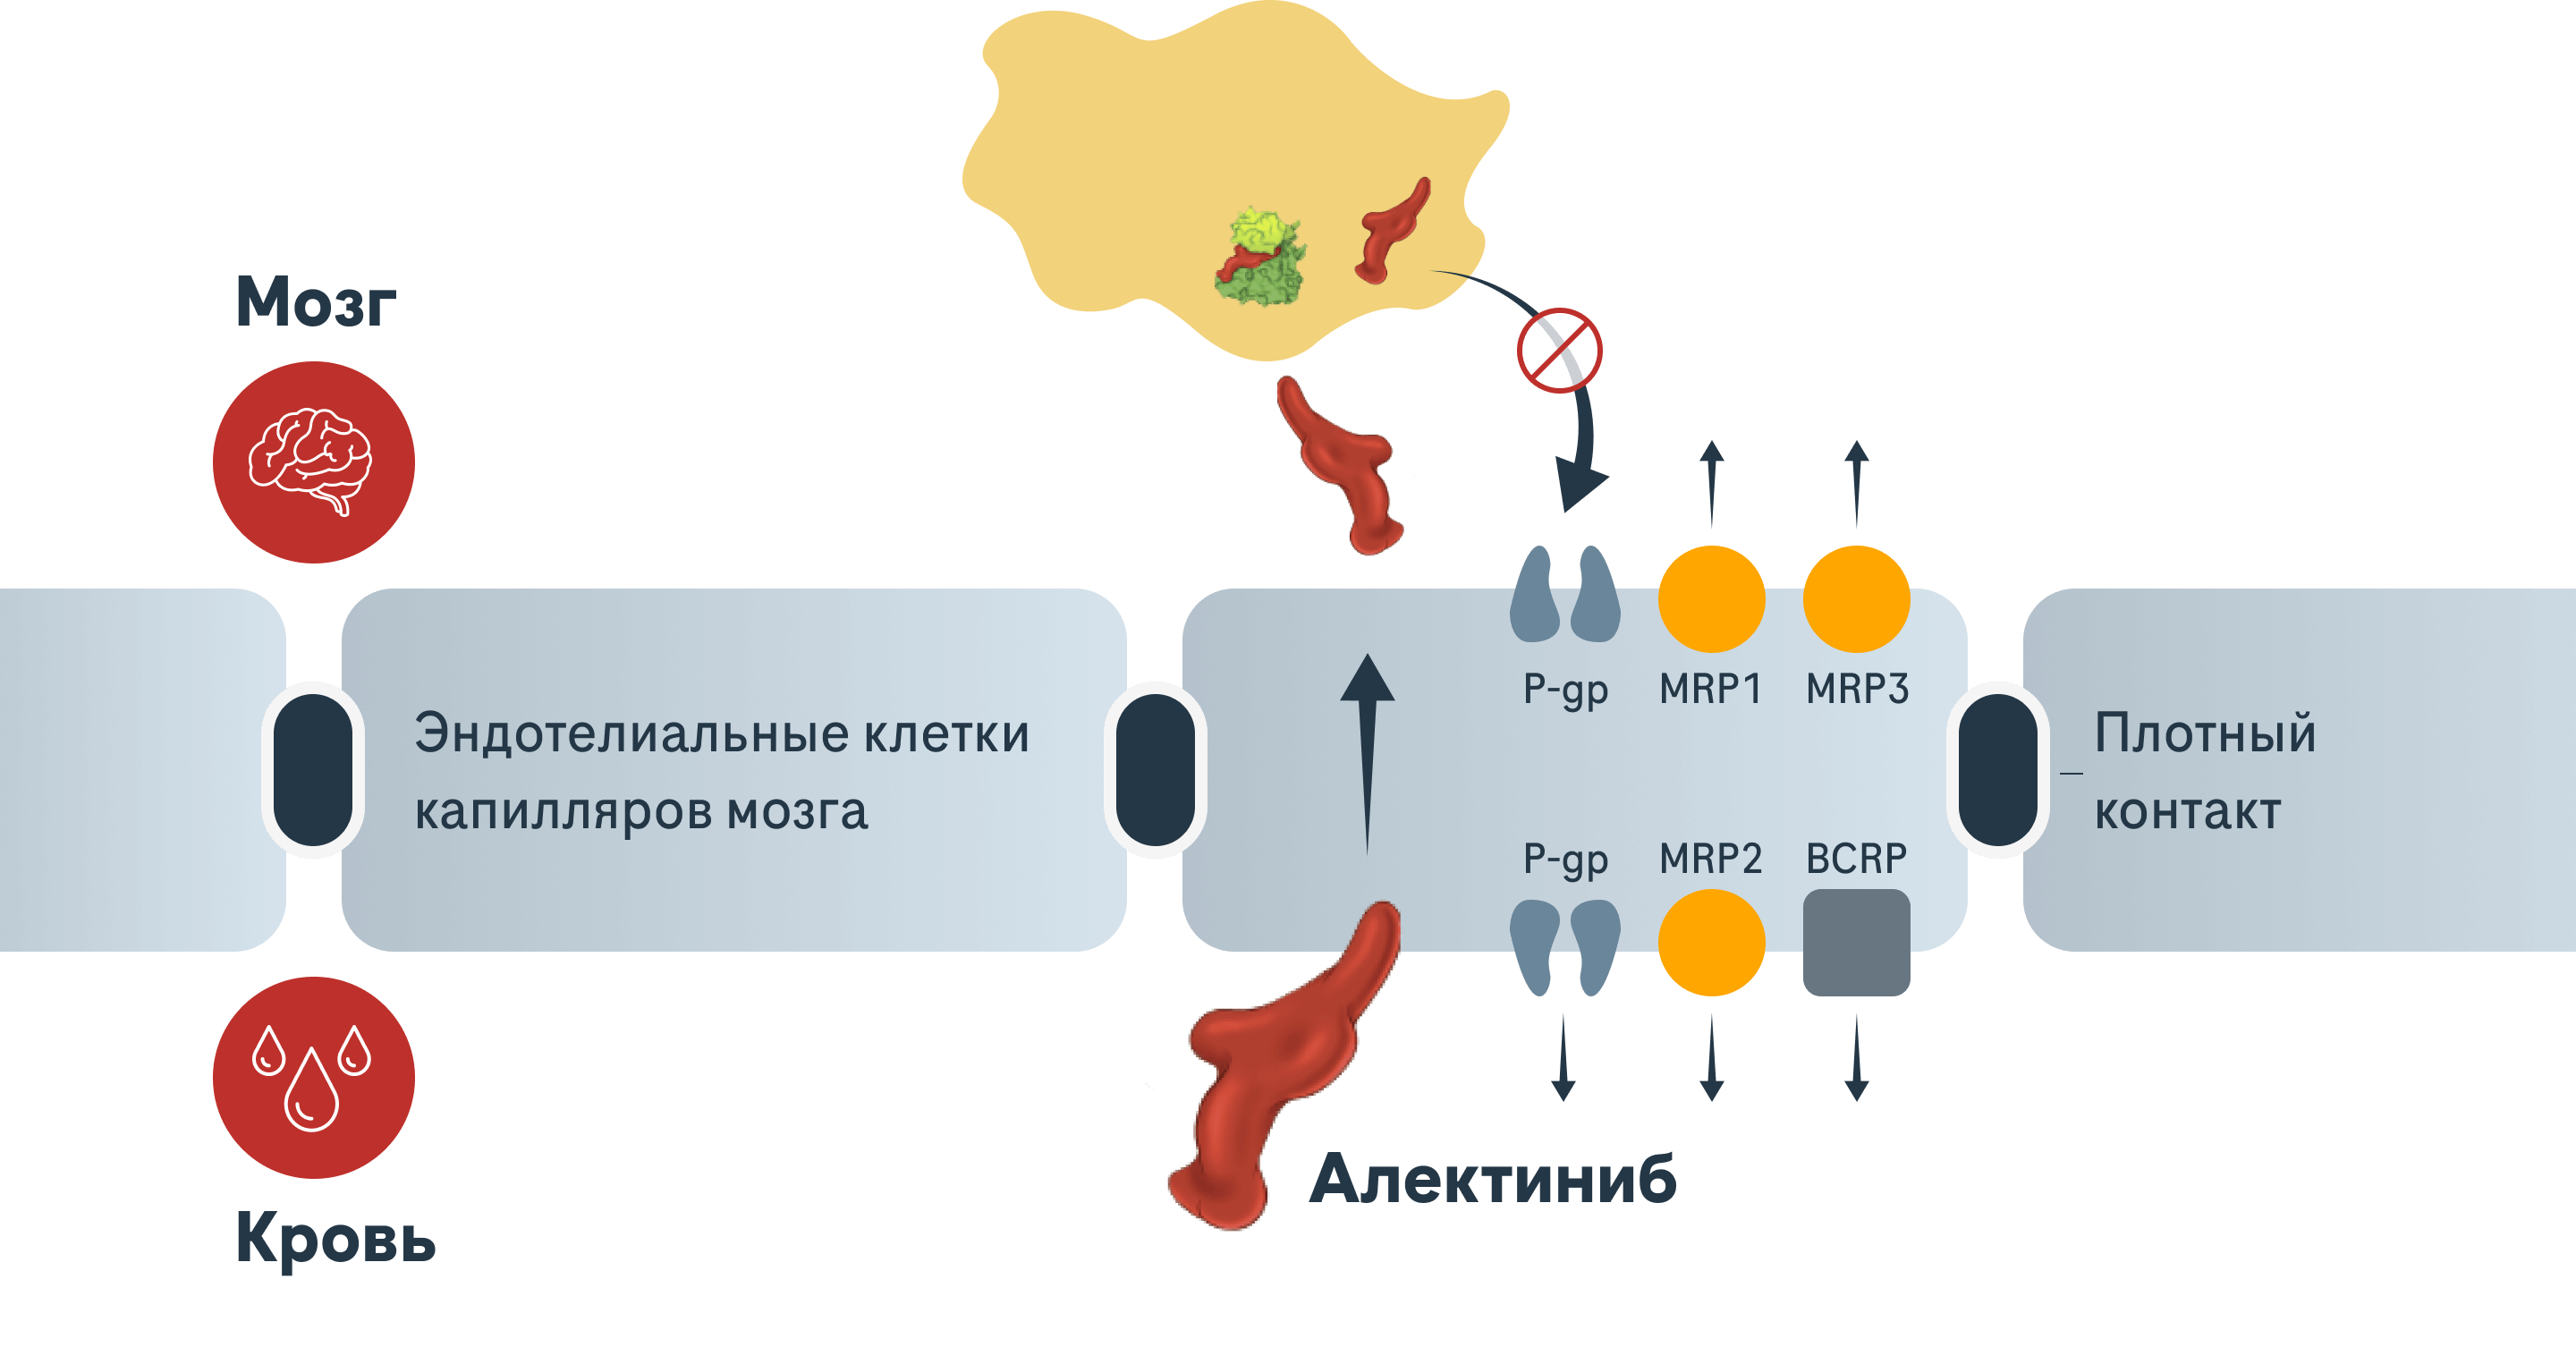

Алектиниб преодолевает гематоэнцефалический барьер и остается в ЦНС1,8

- Исследования in vitro показывают, что Алектиниб не является субстратом P-гликопротеина, но основной активный метаболит Алектиниба (М4) является субстратом P-гликопротеина1

- Субстраты P-гликопротеина обычно выводятся из ЦНС транспортными белками

P-гликопротеина, выстилающими гематоэнцефалический барьер5

Предлагаемое распределение Алектиниба в ЦНС1,2,9-11

ЦНС — центральная нервная система; мНМРЛ — метастатический немелкоклеточный рак лёгкого; ALK — киназа анапластической лимфомы; M4 — основной метаболит M4; BCRP — белок резистентности рака молочной железы; MRP — белок множественной лекарственной резистентности; P-gp — Р-гликопротеин.